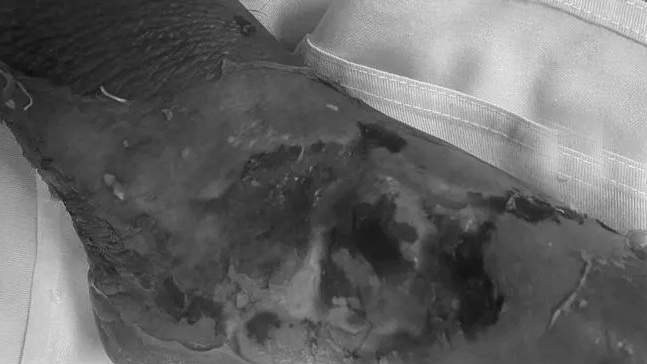

Ca bệnh đầu tiên là trường hợp bệnh nhân Giàng A T. (Nam, 28 tuổi), dân tộc H’mong (Trạm Tấu, Yên Bái). Trong một lần đi rừng do côn trùng đốt làm sưng tấy đùi, T không đi bệnh viện để khám mà lấy thuốc nam đắp. Không lâu sau, vết thương lan rộng hoại tử da từ đùi lan đến bẹn và bìu, hoại tử lộ cả tinh hoàn.

Khi đến Bệnh viện Hữu nghị Việt Đức, bệnh nhân đã lơ mơ, xét nghiệm có dấu hiệu suy gan, thận và gia đình đã có ý định xin cho bệnh nhân về nhà. Sau khi hội chẩn và giải thích cho người nhà, người bệnh nhanh chóng được phẫu thuật trong cấp cứu cắt lọc rộng rãi, lấy bỏ tổ chức hoại tử, cầm máu, để hở vết thương. Sau mổ ngoài hồi sức, truyền dịch, kháng sinh mạnh. Dự kiến người bệnh sẽ tiếp tục còn trải qua vài lần phẫu thuật cắt lọc, khép da và tạo hình da vùng bìu.